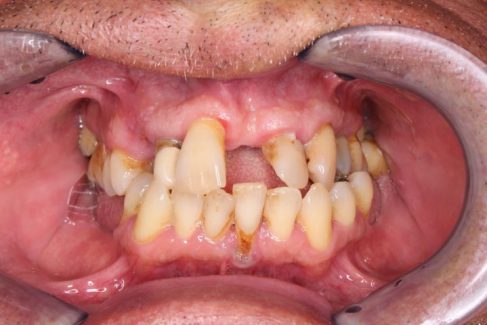

Vorher

Nach der Entfernung der nicht mehr zu rettenden Zähne fertigten wir für den Patienten 28 Metallkeramikkronen an.